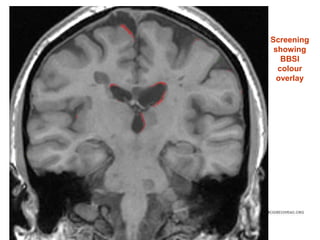

Baseline

Screening

showing

BBSI

colour

overlay

Primary outcome: BBSI change in

whole brain volume (%/year)

• #41 Baseline scan (native space)

• #42 Repeat scans – registered to baseline (spatially aligned)

• #43 Screening (baseline) scan showing BBSI colour overlayRed = intensity (brain tissue) lossGreen= intensity (brain tissue) gainBSI measures this across all the brain surfaces to give a volume of change over time